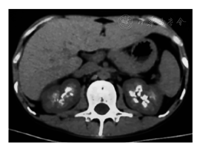

患者男,23岁。22岁时因多饮多尿1个月于2016年11月24日在我院肾内科就诊,门诊以尿崩症收入院。患者多饮多尿逐渐加重,尿量约10 L,比重1.002。每日饮水量约10 L,其中夜间饮水5 L。夜尿3~4次。患者无长期呕吐、腹泻史,且未服用利尿剂等药物。患者系足月顺产,父母非近亲结婚,患者其他直系亲属(父母及姐)均无相似病史。体检:血压117/79 mmHg(1 mmHg=0.133 kPa),身高172 cm,体重40 kg,BMI 13.52 kg/m2。实验室检查:血pH值7.46,血钾2.33 mmol/L,血钠137.00 mmol/L,血氯92.00 mmol/L,血二氧化碳结合力31.38 mmol/L,血钙2.54 mmol/L。尿钾19.32 mmol/L,尿钠51.00 mmol/L,尿氯42.00 mmol/L,尿钙1.33 mmol/L,尿镁1.47 mmol/L。尿肌酐1 777.00 μmol/L。尿钾排泄分数20%,尿钠排泄分数1.2%,尿氯排泄分数1.5%,尿钙/尿肌酐(mol/mol)0.75,尿镁排泄分数8.6%。血肌酐51.00 μmol/L,尿素氮7.59 mmol/L。25羟维生素D3 11.20 ng/ml。甲状旁腺素55.53 pg/ml。肾素-血管紧张素-醛固酮系统检测,卧位:肾素活性11.48 ng·ml-1·h-1,醛固酮192.07 pg/ml;立位:肾素活性>17.76 ng·ml-1·h-1,醛固酮695.76 pg/ml。查抗核抗体、抗可提取核抗原(ENA)谱均阴性。尿常规:尿pH值6.5, 尿比重<1.005,尿隐血1+,尿白细胞1+。超声检查:右肝前叶见强回声光斑0.6 cm×0.5 cm,边界清,双肾窦内多发高回声团,肾窦呈铸形,右肾较大1.9 cm×1.5 cm,左肾较大2.4 cm×2.2 cm。双肾CT示双肾钙质沉积及双肾结石(图1)。双侧99Tcm-MIBI(甲氧基异丁基异腈)甲状旁腺显像未见异常。禁水-加压素试验阴性。患者入院时表现为高血钙、肝右叶钙化灶、双肾结石、双肾钙质沉积,但甲状旁腺素无升高,双侧99Tcm-MIBI甲状旁腺显像未见异常,且复查血钙浓度2.4 mmol/L,故排除甲状旁腺机能亢进症。禁水-加压素试验阴性,排除中枢性尿崩。但患者低血钾、低血氯与原发性肾性尿崩(伴性遗传性肾性尿崩和常染色体隐性或显性肾性尿崩)不符,且患者临床特征与BS相符,故疑诊BS。查纯音听阈测定示双耳听力正常,排除4型BS。静脉+口服氯化钾治疗纠正血钾3.43 mmol/L,血钠144 mmol/L, 血氯102 mmol/L,血二氧化碳结合力30.67 mmol/L,于2016年12月7日出院,未行特殊治疗。2016年12月27日,患者及其家属抽取血样送往青岛金域医学研究所进行第二代高通量测序,对BS和Gitelman综合征(因Gitelman综合征往往与BS存在表型交叉)共7个相关基因(SLC12A1、KCNJ1、CLCNKB、CLCNKA、BSND、CASR、SLC12A3)进行测序,发现KCNJ1基因的2个新的杂合突变,确诊2型BS。一是位于5号外显子的无义突变c.865C>T,突变效应为p.Gln289*,该突变遗传自母亲;二是位于5号外显子的错义突变c.1013G>A,突变效应为p.Arg338Gln,该突变遗传自父亲。经检索人类基因突变库和最新文献,这2个突变是新发现突变。Sanger验证结果见图2。给予患者吲哚美辛0.31 mg·kg-1·d-1,多饮多尿症状当天即明显改善,尿量减少至2 000 ml/d。1周后复查血pH值7.43,血钾3.63 mmol/L, 血钠143.60 mmol/L,血氯103.51 mmol/L,血二氧化碳结合力29.25 mmol/L。随访至今,患者多饮多尿症状无反复,多次复查血酸碱度和电解质指标均正常。